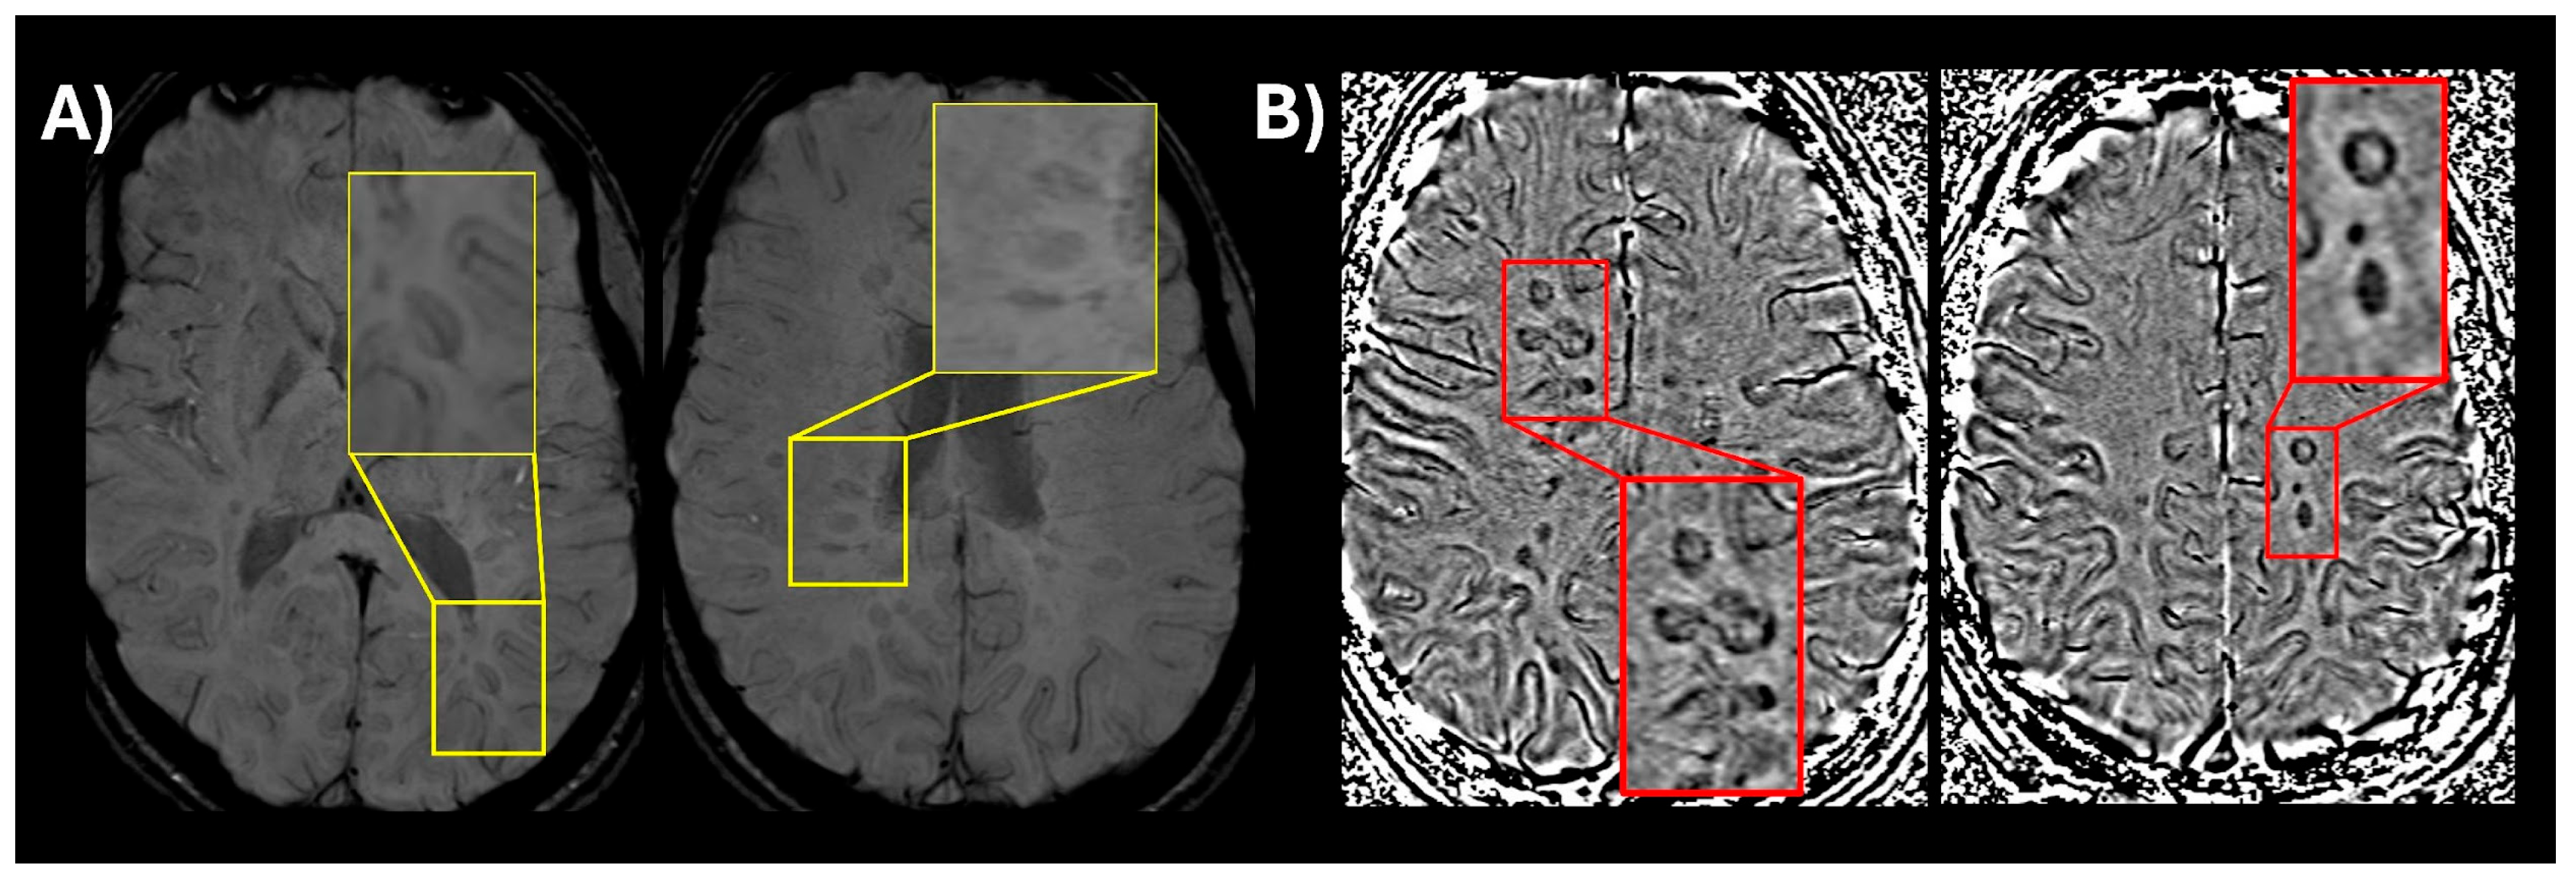

- Sati, P.; George, I.C.; Shea, C.D.; Gaitán, M.I.; Reich, D.S. FLAIR*: A combined MR contrast technique for visualizing white matter lesions and parenchymal veins. Radiology 2012, 265, 926–932. [Google Scholar] [CrossRef]

- Sati, P.; Oh, J.; Constable, R.T.; Evangelou, N.; Guttmann, C.R.G.; Henry, R.G.; Klawiter, E.C.; Mainero, C.; Massacesi, L.; McFarland, H.; et al. The central vein sign and its clinical evaluation for the diagnosis of multiple sclerosis: A consensus statement from the North American Imaging in Multiple Sclerosis Cooperative. Nat. Rev. Neurol. 2016, 12, 714–722. [Google Scholar] [CrossRef] [PubMed]